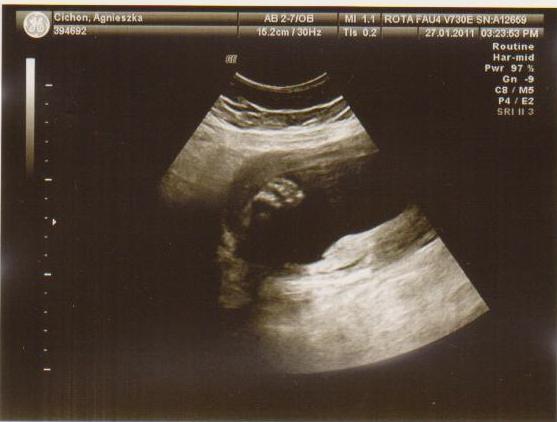

cześć dziewczyny to i ja chciałabym do Was dołączyć, właśnie znalazłam to forum. Mieszkam w Irlandii od 4 lat i mam synka 21 miesięcy, a teraz jestem w 28 tc bliźniaczej :-) dwie dziewczynki dwujajowe :-) też mnie trochę przeraża poród bliźniaków ale trzeba jakoś urodzić ;-) Pierwszy poród miałam jak marzenie szybko, sprawnie i nawet bez znieczulenia, mam nadzieję że i tym razem bęzie podobnie.

Hej podwojne mamunie:-)Ja juz rozpakowana dawno mamusia dubeltowka.Gratuluje wam serdecznie i witam w gronie tych wybranych hihiNiczego sie nie bojcie.Ciaxa blizniacza jest pod specjalna opieka.Czekaja was czeste wizyty w szpitalu i czeste ogladanie maluszkow na usg :-)